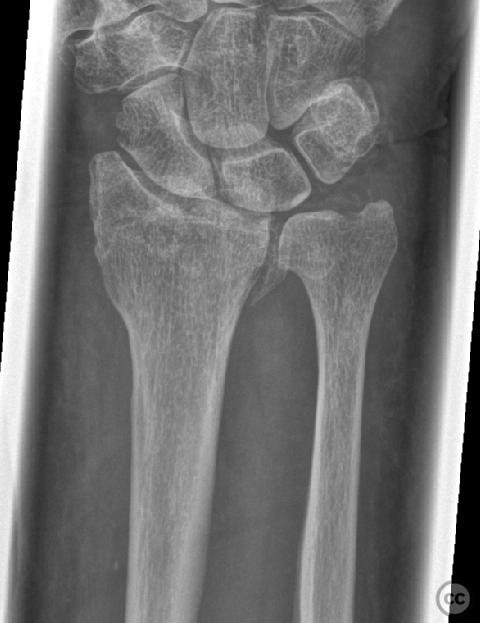

Clinical and radiological findings:  A 72-year-old female sustained a multifragmentary, dorsally displaced distal radius fracture after a fall down stairs. Initial reduction revealed a 180-degree flipped fragment of the volar ulnar articular margin, unreducible by closed means. There was no mention of associated neurovascular compromise or open injury. Radiographs and intraoperative fluoroscopy confirmed the presence of a multifragmentary intra-articular fracture (AO/OTA 23-C3), with a flipped volar ulnar fragment and radial styloid impaction. The distal radioulnar joint alignment was restored postoperatively.

Planning remarks:  The preoperative plan was for open reduction and internal fixation via an Extended (eFCR) volar approach, with specific attention to direct visualization and reduction of the flipped volar ulnar articular fragment, anatomical reduction of the radial styloid, and fragment-specific fixation using mini-fragment plates and provisional Kirschner wires.